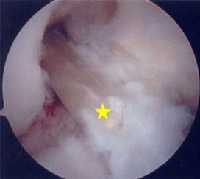

Arthroscopic view of ACL graft [yellow star] in position.